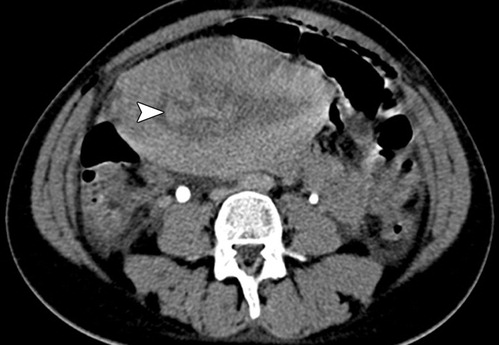

Figure 3: Axial contrast material–enhanced CT image of a normal postpartum uterus, obtained 12 hours after vaginal delivery reveals an enlarged uterus containing a low-attenuation central area corresponding to intrauterine blood debris and fluid. Fresh blood clots are seen as hyperattenuating foci (arrowhead). (Reprinted with permission) [5].

figure 3